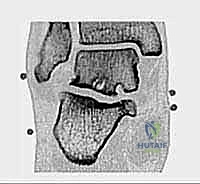

* التصوير بالرنين المغناطيسي (MRI): هو المعيار الذهبي. يكشف بدقة متناهية عن التهابات الأوتار (مثل FHL)، ارتشاح السوائل، تمزقات الأربطة، ووذمة نخاع العظم (Bone Marrow Edema) التي لا تظهر في الأشعة العادية.

* الأشعة المقطعية (CT Scan): تُستخدم في حالات معينة لعمل خريطة ثلاثية الأبعاد للكسور القديمة أو التكلسات العظمية المعقدة قبل الجراحة.

هي إصابات بؤرية تصيب الغضروف المفصلي والعظم الذي تحته، غالباً في قبة عظم الكاحل (Talar Dome). إذا كانت هذه الآفات تقع في الجزء الخلفي من المفصل، فإن الوصول إليها وعلاجها يكون مثالياً عبر المنظار الخلفي.